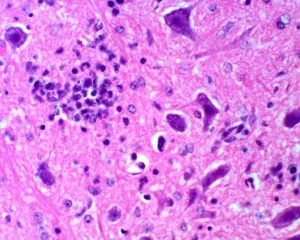

Once infected by virus, nerve cells of the brain will attract large numbers of white blood cells to clear the infection. Among these, a primitive group known as monocytes, newly minted by the bone marrow, causes inflammation that amplifies the immune response. However, this behaviour can also cause lethal damage. In a novel therapeutic strategy, we have used immune modifying nanoparticles to modulate monocyte migration and function, to reduce inflammation, increase healing and enable survival, not just in viral infection of the brain, but in a range of other diseases in which inflammation is excessive.

Once infected by virus, nerve cells of the brain will attract large numbers of white blood cells to clear the infection. Among these, a primitive group known as monocytes, newly minted by the bone marrow, causes inflammation that amplifies the immune response. However, this behaviour can also cause lethal damage. In a novel therapeutic strategy, we have used immune modifying nanoparticles to modulate monocyte migration and function, to reduce inflammation, increase healing and enable survival, not just in viral infection of the brain, but in a range of other diseases in which inflammation is excessive.